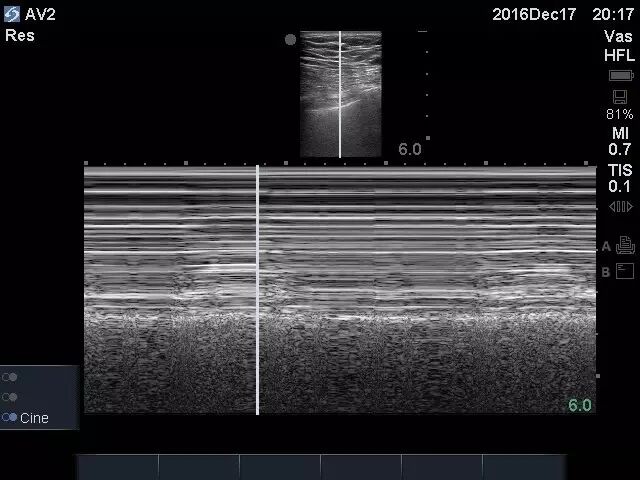

经治疗,患者血压回升,症状好转,意识转清。操作过程中可实时观察穿刺针位置(图3),一次性进入腋静脉,操作过程安全快速(图4)。

图4 术后对同侧胸腔行M超扫查见肺部呈现“沙滩征”,提示无气胸发生